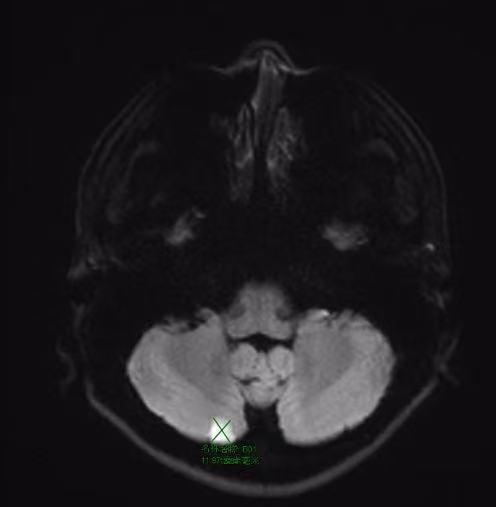

视觉障碍呈现为视野缺损又或者视物重影,致使如此的根源是脑干动眼神经核缺血,行走不稳意味着小脑被累及,患者存在突然没办法走直线的可能性,要是出现单侧肢体麻木,亦或者面部感觉异常,这表明感觉神经通路已然受损,必须马上就医。

当血栓脱落之后随着血流进入到脑内血血管处,就会如同塞子相同堵塞住血管,致使脑组织出现缺血坏死的状况 。